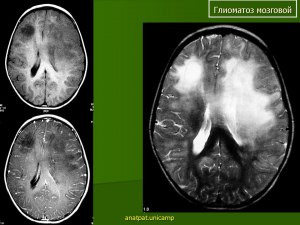

Что такое глиоматоз?

Глиоматоз - это опухолевое заболевание, которое характеризуется наличием опухолей в головном мозге. Это тип рака, который начинается в глиальных клетках, которые поддерживают нервные клетки в мозге.